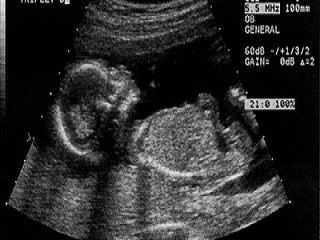

УЗИ на 29 неделе беременности

Ультразвуковое исследование на этом сроке проводится только строго по показаниям. Его назначают, если врач подозревает отклонения во внутриутробном развитии малыша и хочет убедиться в своих догадках.

Чтобы оценить темпы развития ребенка, узист проводит замеры лобно-затылочной доли, окружности головы, живота и изучает бипариетальные параметры. На мониторе врач смотрит положение малыша и определяет, занял ли он необходимую для рождения позу.

Зачастую малыш уже перевернулся головой вниз, готовясь пройти через родовые пути.

Также строго по показаниям проводится УЗИ на 29 неделе. Исследование назначается в том случае, если врач хочет убедиться в правильном внутриутробном развитии плода. Для оценки темпов развития ребенка диагност измеряет такие показатели, как бипариетальный и лобно-затылочный размеры, окружность головы и живота и др. На УЗИ специалист непременно определит положение, которое плод занимает в утробе матери. В большинстве случаев малыш уже перевернулся головой вниз, готовясь к выходу через родовые пути.

Фото УЗИ на 29-й неделе:

Зачастую в этот период УЗИ не проводится. Но Ваш гинеколог может принять решение о такой необходимости. Тогда специалисты на этом сроке смогут увидеть пол ребенка со 100% гарантией.

В этот период в обязательном порядке производится оценивание показателей плаценты и ее состояние. Толщина ее будет около 29 сантиметров. Степень зрелости все также нулевая.

Диагност очень тщательно проведет обследование внутренних органов и строение тела малыша. Изучит, как органы развиваются и соответствуют ли они среднестатистической норме. В зависимости от показаний веса плода могут быть внесены изменения в Ваше питание.

Очень кропотливо производят осмотр сердечка и измерение скорости его биения.

Если раньше не удалось определить пол будущего ребенка, то на 29 неделе это можно узнать наверняка при помощи УЗИ. Проводя ультразвуковое исследование, оценивают не только состояние плода, но и плаценту. Ее нормальная толщина на данном этапе составляет 29 мм, а степень зрелости должна быть нулевой. Если обнаружится, что вес малыша превышает норму, беременной скорректируют рацион питания. Важным показателем является сердцебиение плода.

УЗИ на этом сроке делать необходимо для того, что убедиться в состоянии малыша, плаценты и самой беременной.

Определяется размер плода, состояние плаценты, состояние и количество околоплодных вод, размеры и положение матки, а также другая важная информация. УЗИ – это самый простой и безболезненный способ выявить всю необходимую информацию. Кроме того, УЗИ не только полезно, но и приятно. Ведь, это лишний повод взглянуть на своего, уже сформировавшегося малыша.

Для тех, кто не смог узнать пол ребенка раньше – УЗИ в 29 недель беременности сможет сообщить эту информацию со 100% гарантией. При желании, можно сделать снимок, или, даже, создать видео файл вашего, еще нарожденного, но уже развитого малыша.